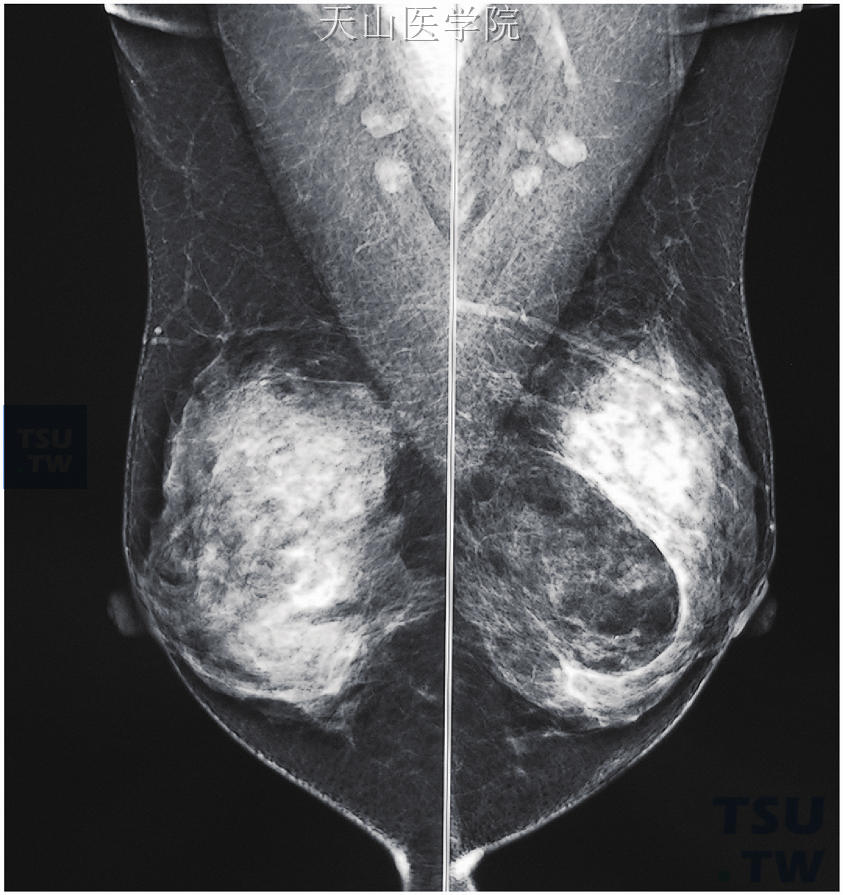

• 乳腺良性肿瘤的X线表现

纤维腺瘤纤维腺瘤是最常见的乳腺良性肿瘤,由增生的乳腺纤维组织和导管共同构成,具有双向分化的特点。多数人认为纤维腺瘤为肿瘤,但近年来也有人认为是正常乳腺小叶增生的结果。